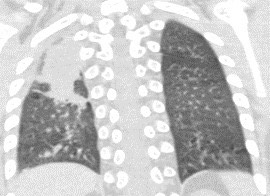

1934. У пациента 3 лет с диагнозом «острый лимфобластный лейкоз» на фоне полихимиотерапии появилась лихорадка, была выполнена компьютерная томография грудной клетки, рентгенологическая картина соответствует